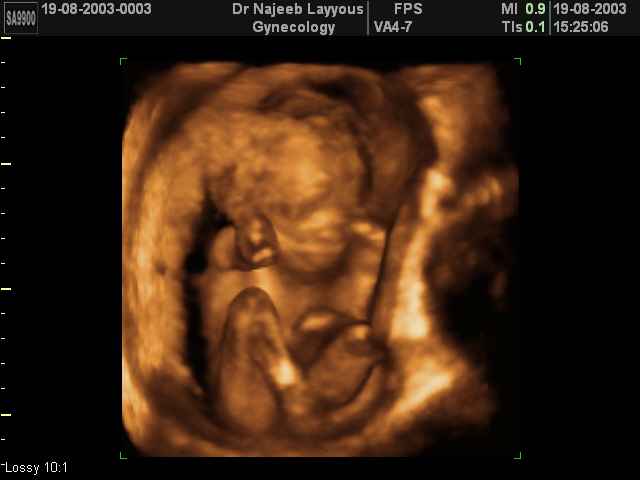

- تصرفات الجنين داخل الرحم

- صور لتصرفات الجنين داخل الرحم

صور لتصرفات الجنين داخل الرحم بجهاز الالتراساوند ثلاثي الأبعاد | الدكتور نجيب ليوس